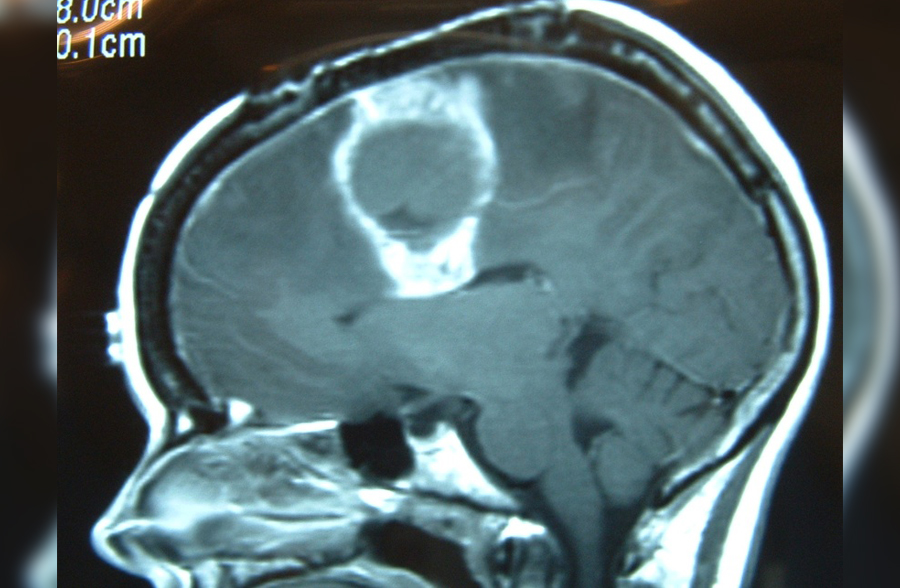

Tumores cerebrales

Los tumores se manifiestan por dolor de cabeza que no responde al manejo habitual.

También puede haber convulsiones, alteraciones de la fuerza de un lado del cuerpo o

afectación de la movilidad ocular o de la cara, vértigo, nauseas, vómitos, falta de coordinación, transtornos hormonales o visuales etc.

¡Es muy importante su detección temprana!